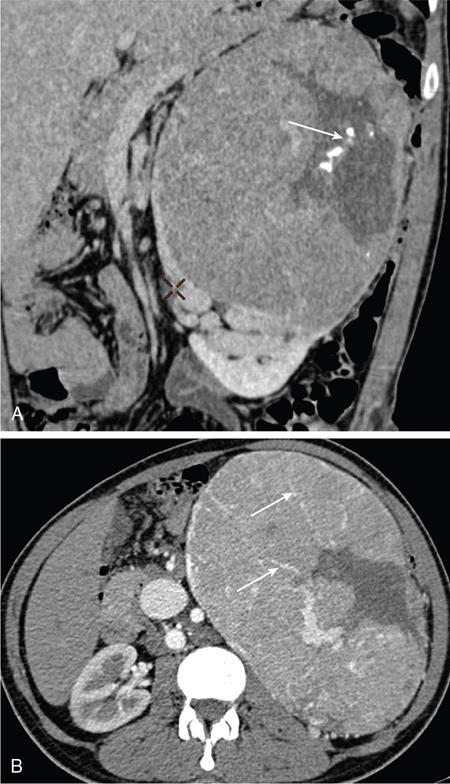

IMAGING OF RENAL MALIGNANCIES IN ADULTS Aparna Katdare, Palak Bhavesh Popat, Nilesh P. Sable, Ganesh Bakshi, Suyash Kulkarni Detection of renal masses has increased remarkably in recent times owing to wide-spread use of cross-sectional imaging. Imaging plays an important role in characterizing renal masses and is indispensable in treatment planning in renal malignancies. The most commonly encountered malignant renal masses in practice include renal cell carcinoma (RCC), urothelial carcinoma, lymphoma and metastases. Urothelial carcinoma and lymphoma have been covered in detail in separate chapters. RCC constitutes nearly 90% of all renal malignancies with a higher incidence in North America and Europe than India, Africa and China. With an increase in the number of cross-sectional studies performed, especially in Western population, the incidental diagnosis of RCC has increased in recent times, with such incidentally diagnosed lesions presenting at earlier stages with better prognosis and reduced rates of recurrence. The median age of presentation of RCC is 64 years according to the Surveillance, Epidemiology and End Results (SEER) program database and almost a decade earlier in Indian population, with a definite increasing risk of RCC with increasing age. Males are affected about 2–3.5 times more than females. In the Indian population, patients have been seen to present at a later stage as compared to the Western population. Amongst the various postulated risk factors, there is convincing evidence that smoking, hypertension, obesity and acquired renal cystic disease increase the risk of RCC. Alcohol intake and physical activity have been found to be associated with reduced risk of RCC. Trichloroethylene and cadmium exposure have been postulated as likely causes as well. Two to four per cent of RCCs are hereditary, with association of various genetic disorders such as Von Hippel Lindau (VHL) syndrome, hereditary papillary renal carcinoma, hereditary leiomyomatosis RCC, Birt-Hogg-Dube syndrome, chromosome 3 translocation and tuberous sclerosis (TCS1, TCS2). The WHO classification of 2016 (Table 11.25.1.1) stratifies tumours of the kidney into different subtypes based on cytoplasmic and architectural features, tumour location, background renal disease and molecular alterations. Clear cell renal cell carcinoma Multilocular cystic renal neoplasm of low malignant potential Papillary renal cell carcinoma Hereditary leiomyomatosis and renal cell carcinoma-associated renal cell carcinoma Chromophobe renal cell carcinoma Collecting duct carcinoma Renal medullary carcinoma MiT family translocation renal cell carcinomas Succinate dehydrogenase-deficient renal carcinoma Mucinous tubular and spindle cell carcinoma Tubulocystic renal cell carcinoma Acquired cystic disease-associated renal cell carcinoma Clear cell papillary renal cell carcinoma Renal cell carcinoma, unclassified Papillary adenoma Oncocytoma 8310/3 8316/1a 8260/3 8311/3* 8317/3 8319/3 8510/3a 8311/3a 8311/3 8480/3a 8316/3a 8316/3 8323/1 8312/3 8260/0 8290/0 Metanephric adenoma Metanephric adenofibroma Metanephric stromal tumour 8325/0 9013/0 8935/1 Nephrogenic rests Nephroblastoma Cystic partially differentiated nephroblastoma Paediatric cystic nephroma 8960/3 8959/1 8959/0 Clear cell sarcoma Rhabdoid tumour Congenital mesoblastic nephroma Ossifying renal tumour of infancy 8964/3 8963/3 8960/1 8967/0 Leiomyosarcoma Angiosarcoma Rhabdomyosarcoma Osteosarcoma Synovial sarcoma Ewing sarcoma Angiomyolipoma Epithelioid angiomyolipoma Leiomyoma Haemangioma Lymphangioma Haemangioblastoma Juxtaglomerular cell tumour Renomedullary interstitial cell tumour Schwannoma Solitary fibrous tumour 8890/3 9120/3 8900/3 9180/3 9040/3 9364/3 8860/0 8860/1a 8890/0 9120/0 9170/0 9161/1 8361/0 8966/0 9560/0 8815/1 Cystic nephroma Mixed epithelial and stromal tumour 8959/0 8959/0 Well-differentiated neuroendocrine tumour Large cell neuroendocrine carcinoma Small cell neuroendocrine carcinoma Phaeochromocytoma 8240/3 8013/3 8041/3 8700/0 Renal haematopoietic neoplasms Germ cell tumours The morphology codes are from the International Classification of Diseases for Oncology (ICD-O) {917A}, Behaviour is coded/0 for benign tumours; /1 for unspecified, borderline or uncertain behaviour; /2 for carcinoma in situ and grade III intraepithelial neoplasia; and /3 for malignant tumours. The classification is modified from the previous WHO classification (756A), taking into account changes in our understanding of these lesions. aNew code approved by the IARC/WHO Committee for ICD-O. Of these, the most common entity is the clear cell subtype, while papillary and chromophobe subtypes are less common. The different subtypes show varied biological behaviour, treatment response and prognosis. The 2017 guidelines by American Urological Association (AUA) as well as 2019 guidelines by European Society of Medical Oncology (ESMO) recommend multiphase cross-sectional imaging by either CT or MRI for renal mass characterization and staging. AUA 2017 guidelines recommend renal mass characterization on the basis of tumour complexity, contrast enhancement and presence or absence of fat. MRI has an upper hand over CT in characterizing subtle mass enhancement, cystic lesions and lesions less than 2 cm. ESMO recommends contrast-enhanced CT study of the chest, abdomen and pelvis for renal mass staging. Bone scan and brain CT or MRI can be considered if indicated by clinical or laboratory investigations. For characterization of renal masses, a multiphase CT or MRI study is recommended. CT study constitutes an unenhanced study followed by contrast injection and acquisition of corticomedullary phase at 40 seconds, nephrographic phase at around 100 seconds and delayed phase at around 5 minutes. MRI protocol includes T2-weighted single-shot fast spin-echo 2D sequences, axial T1-weighted 2D sequence with in-phase and opposed-phase gradient echo imaging, precontrast and postcontrast imaging with a 3D T1-weighted spoiled gradient recalled sequences in corticomedullary phase at 30 seconds, nephrographic phase at 100 seconds, 180–210 seconds and delayed phase imaging at 5 minutes and diffusion-weighted imaging with multiple b-values 0–50, 400–500 and 800–1000 s/mm2. The ACR White Paper on CT imaging of incidental renal mass recommends using the following descriptors for characterizing renal masses: Given the prognostic implications, it is worthwhile for radiologists to know the imaging features that may help discriminate between the common histological subtypes of RCC on various imaging modalities. This is the most common histological type of RCC, accounting for about 70% of cases. These are exophytic tumours with a heterogeneous appearance due to the presence of necrosis, intratumoural haemorrhage, cystic components with septations and calcific foci and hence have a more heterogeneous appearance on cross-sectional imaging than the other subtypes (Fig. 11.25.1.1). Necrosis is seen more often in larger masses and higher tumour grades (Fig. 11.25.1.2). On CT, depending on the tumour composition, these are seen as heterogeneous lesions, show marked contrast enhancement in the corticomedullary phase with washout on nephrogenic phase (Fig. 11.25.1.2). On MRI, these characteristically show high signal intensity on T2W sequences (Fig. 11.25.1.3). The presence of intracytoplasmic fat in the clear cells of the tumour is reflected in the loss of signal in opposed phase images on chemical shift imaging, which is seen in nearly 60% of these tumours. A pseudocapsule may be seen, which is best appreciated on T2-weighted imaging on MRI; the presence of a pseudocapsule has a high negative predictive value for perinephric extension (Figs. 11.25.1.3 and 11.25.1.4). Conversely, larger tumours with higher grades often have interrupted pseudocapsule and hence tend to be irregular, spread into the perinephric fat with renal vein and inferior vena cava (IVC) invasion (Figs. 11.25.1.5 and 11.25.1.6). On diffusion-weighted imaging, clear cell RCCs have been seen to have higher ADC values than nonclear cell RCCs, and lower-grade tumours have been seen to have higher ADC values than higher-grade tumours. The clear cell variant has worse prognosis than the papillary and chromophobe subtypes, presenting at a more advanced stage and being more likely to recur or metastasize (Fig. 11.25.1.7), with lower 5-year survival rates at 44%–69% as compared to 78%–92% for the other two. Papillary RCC comprises about 10%–15% of RCCs. These are slow-growing tumours and hence are well-marginated in contrast to clear cell RCC. As they are hypovascular, their enhancement on CT is significantly less than clear cell RCC (Fig. 11.25.1.8). These show characteristically low signal on T2W images on MRI (Fig. 11.25.1.9). Intracytoplasmic or macroscopic fat is less often seen on MRI imaging as compared to the clear cell variants. Larger tumours tend to be more heterogeneous (Fig. 11.25.1.10). These tumours may sometimes show cystic appearances, mural projections or blood degradation products. Calcifications are more common in papillary variants than clear cell RCC. Multifocality and bilaterality are also more common in these tumours than clear cell variants. These account for about 5% of RCCs. These are less aggressive, more homogeneous and hypovascular lesions than clear cell variants, with intensity of contrast enhancement on cross-sectional imaging being midway between clear cell and papillary variants. They show low to intermediate T2 signals on MRI. A characteristic feature is the presence of a central scar and spoke-wheel enhancement, the latter being a histopathological and imaging similarity between these tumours and oncocytoma (Fig. 11.25.1.11). Other subtypes of RCC are much less common but some may show distinct imaging findings. Multilocular cystic RCCs have excellent prognosis and lack mural nodules within the cystic components, unlike clear cell RCCs with cystic degeneration which show mural nodules. Collecting duct carcinomas, on the other hand, are aggressive tumours with poor prognosis and have medullary origin, and therefore appear similar to transitional cell carcinomas on imaging. Medullary RCCs are associated with sickle cell disease and sickle cell trait and are seen as infiltrating intracalyceal obstructive lesions with associated nodal disease. The imaging work-up of a suspected RCC is aimed at: Localized renal cancer is defined as a disease confined to the renal capsule and refers mainly to stage I and II disease. Nearly 70% of RCCs, especially the lower-stage lesions, are incidentally diagnosed on cross-sectional imaging. Also, amongst incidentally diagnosed renal lesions less than 4 cm in size, about 20% turn out to be benign on histopathology. Asymptomatic incidentally diagnosed small renal masses have an indolent course and better prognosis. Nephron-sparing surgery (NSS) has gathered momentum in recent years due to promising results and prognoses in small lesions. The 2017 AUA guidelines for localized renal masses describe restricted and well-defined indications for radical nephrectomy, bigger role of nephron-sparing procedures such as partial nephrectomy, tumour enucleation and thermal ablation, as well as increasing role for biopsy as well as active surveillance of such lesions. Hence, imaging findings in these lesions become critical in charting management of these patients. The imaging features of common histopathological subtypes of RCCs have already been discussed above. Signal intensity on T2W images and corticomedullary phase enhancement have been seen to be independent predictors of clear cell and papillary RCCs. Further, T2 signal homogeneity can be a predictor for slower growth rate. Hence, in general, multiparametric MRI studies have been shown to be effective in small renal mass characterization and can subsequently guide decisions regarding biopsy, surgery or surveillance. CT is a good alternative in patients with contraindication to MRI. For cystic renal lesions, the Bosniak classification, which stratifies the risk of neoplasia in cystic renal lesions based on the complexity of their appearance (wall thickness, septations, solid component), can be used effectively to decide further course of management. The Bosniak classification originally applies to CT findings but can logically be extrapolated to MRI, USG and Contrast Enhanced Ultrasound (CEUS) as well. Bosniak I and II cysts are benign while Bosniak IIF, III and IV cysts show progressively increasing risk of neoplasia. Given the more indolent course of cystic RCCs as compared to solid lesions and possible complications of interventions, lately there has been a case for even the type III and IV cysts, which previously would be operated, to be followed up, especially if patient has existing comorbidities or if the solid component is minimal. Initial follow-up would be at 6 months, followed by annual imaging. AUA 2017 guidelines recommend considering renal mass biopsy if haematologic, metastatic, inflammatory or infectious aetiology is suspected. Once the need for surgery is established in a localized disease, NSS may be considered for stage Ia and Ib disease. To predict perioperative outcomes in NSS, various scoring systems have been proposed for preoperative renal mass evaluation, such as R.E.N.A.L. nephrometry score, PADUA score (Preoperative aspects and dimensions used for anatomical classification), C-index method and mathematical tumour contact surface area (CSA). The popular R.E.N.A.L. nephrometry score takes into account various tumour descriptors that help decide the technical feasibility of NSS and predict surgical outcomes. These include tumour radius, exo/endophytic location, nearness to collecting system or renal sinus, anterior/posterior location and location with reference to polar lines. These descriptors need to be commented upon diligently while reporting renal masses (Table 11.25.1.4). Higher scores are seen to correlate with ischaemia time, postoperative urologic complications, higher grade and mortality. These include organ-confined tumours more than 7 cm in size, or tumours of any size which show regional nodal involvement and/or invasion of perinephric tissues but confined to Gerota’s fascia. These include renal vein and IVC invasion (luminal and mural). Generally, radical nephrectomy is recommended by the National Comprehensive Cancer Network (NCCN) in stage II and III RCCs. Both CT and MRI are effective in diagnosing locally advanced disease in RCC. The loss or interruption of pseudocapsule is seen in more infiltrative and aggressive disease and is best seen on MRI. Local infiltration may be in the form of contiguous spread to perinephric tissues or discrete deposits in perinephric fat (Fig. 11.25.1.15). IVC or renal vein invasion could be in the form of intraluminal thrombosis or invasion of the vessel wall and have implications on surgical approach and outcomes. Tumour thrombus can be distinguished from bland thrombus by confirming vascularity within the thrombus on imaging. Doppler evaluation, CEUS, CT and MRI can all be helpful for the same. MRI is better than other modalities for venous evaluation, especially for mural invasion and IVC invasion (Figs. 11.25.1.16 and 11.25.1.17). Right-sided tumours, anteroposterior IVC diameter of 2.4 cm or more at the level of renal hilum and complete IVC occlusion at this level are associated with higher risk of IVC resection. About 16% of patients with RCC have metastases at diagnosis and about 20%–30% of patients operated for local disease develop recurrence or metastases at a later date. The recurrent disease occurs most commonly within 3 years of diagnosis and uncommonly even later in young patients or large tumours. The most common sites of metastases from RCC are lungs, liver, bones, nodes, adrenals and brain. CT scan is the preferred modality for primary staging and surveillance for metastases because of its widespread availability and versatility for diagnosing bone and soft tissue lesions. MRI is preferred for looking for recurrence in postablative lesions, wherein these are seen as new enhancing lesions or show increase in the size of preexisting enhancing components. 18FFluorodeoxyglucose – Positron Emission Tomography (PET)/CT and PET/MRI may be helpful to look for metastatic disease as well. 18FSodium fluoride – PET/CT has been found to be better than CT and bone scan in detecting osseous metastases. RCC is a relatively radiation-resistant tumour, and treatment options tilt in favour of surgical procedures for localized and locally advanced diseases. For metastatic disease, post-risk assignment, the treatment has to be planned. Treatment can be offered as per size and the clinical stage.